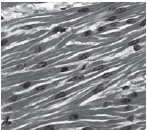

Укажіть зображення тканини, клітини якої здатні до скорочення.